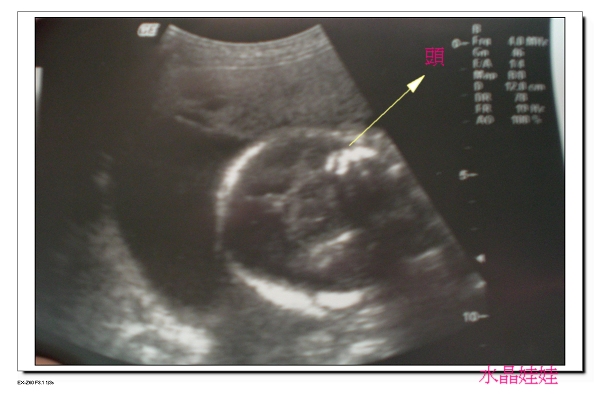

本次重點醫生主要是檢測多錢的胎頭是否降到準備位置,

但醫生檢測後,

判斷多錢的胎頭是朝下、胎位算正的,可是卻尚未降到準備位置。

多錢的頭依然是朝下的,